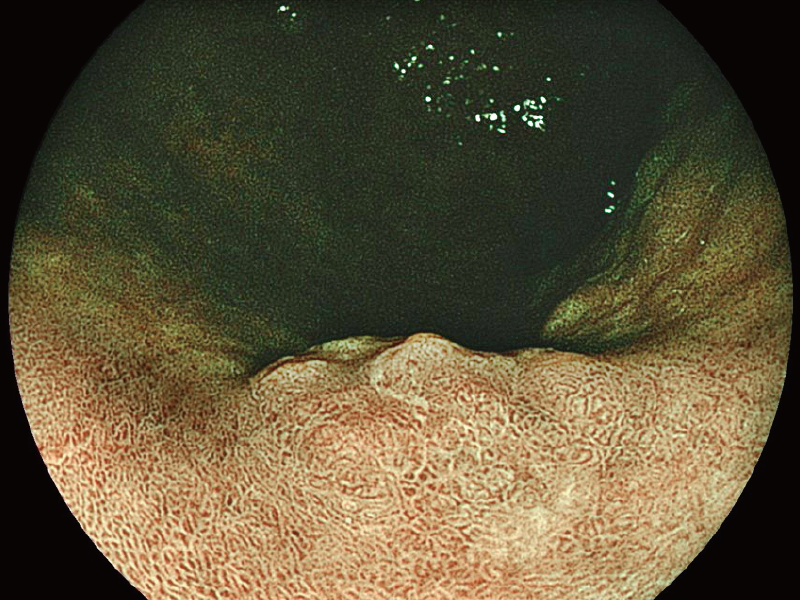

White Light Imaging

BLI (Blue Light Imaging)

*3 The images are not strictly close observation at 2 mm